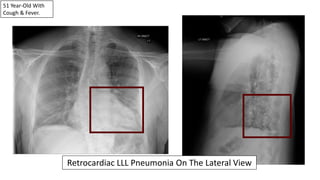

51 Year-Old With

Cough & Fever.

Pneumonias Can Be Subtle On The PA View Alone.

Retrocardiac LLL Pneumonia On The Lateral View